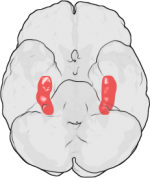

图片[编辑 | 编辑源代码]

- Hippocampus and seahorse cropped.JPG

大脑的海马区(左)和海马(右)。